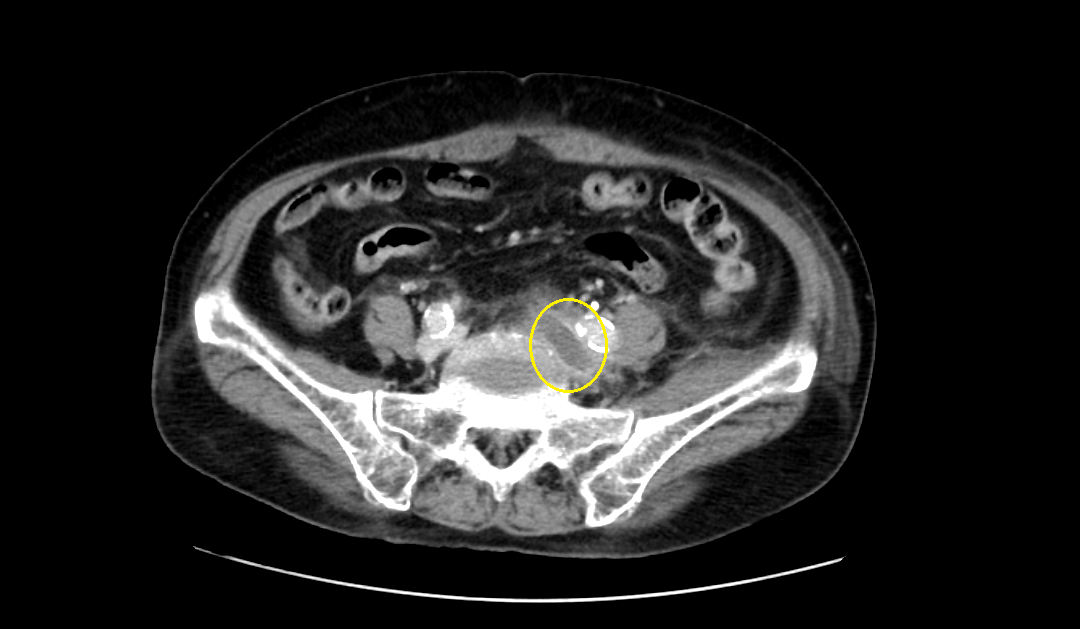

영상은 머리에 가까운 복부에서 다리 쪽으로 가는 순서로 나열하였다.

CT영상을 보면 좌측 장골정맥과 우측 장골동맥이 교차하는 지점에서부터 다리 말단 쪽으로 내려가며, 총장골정맥-외장골정맥-총대퇴정맥-표대대퇴정맥-오금정맥-경골정맥까지 혈전이 차있는 모습을 확인할 수 있었다.

Acute DVT, left CIV, EIV, IIV, CFV, SFV, popliteal and crural veins with compression of left CIV between vertebra and right CIA, c/w acute DVT with May Thurner syndrome.